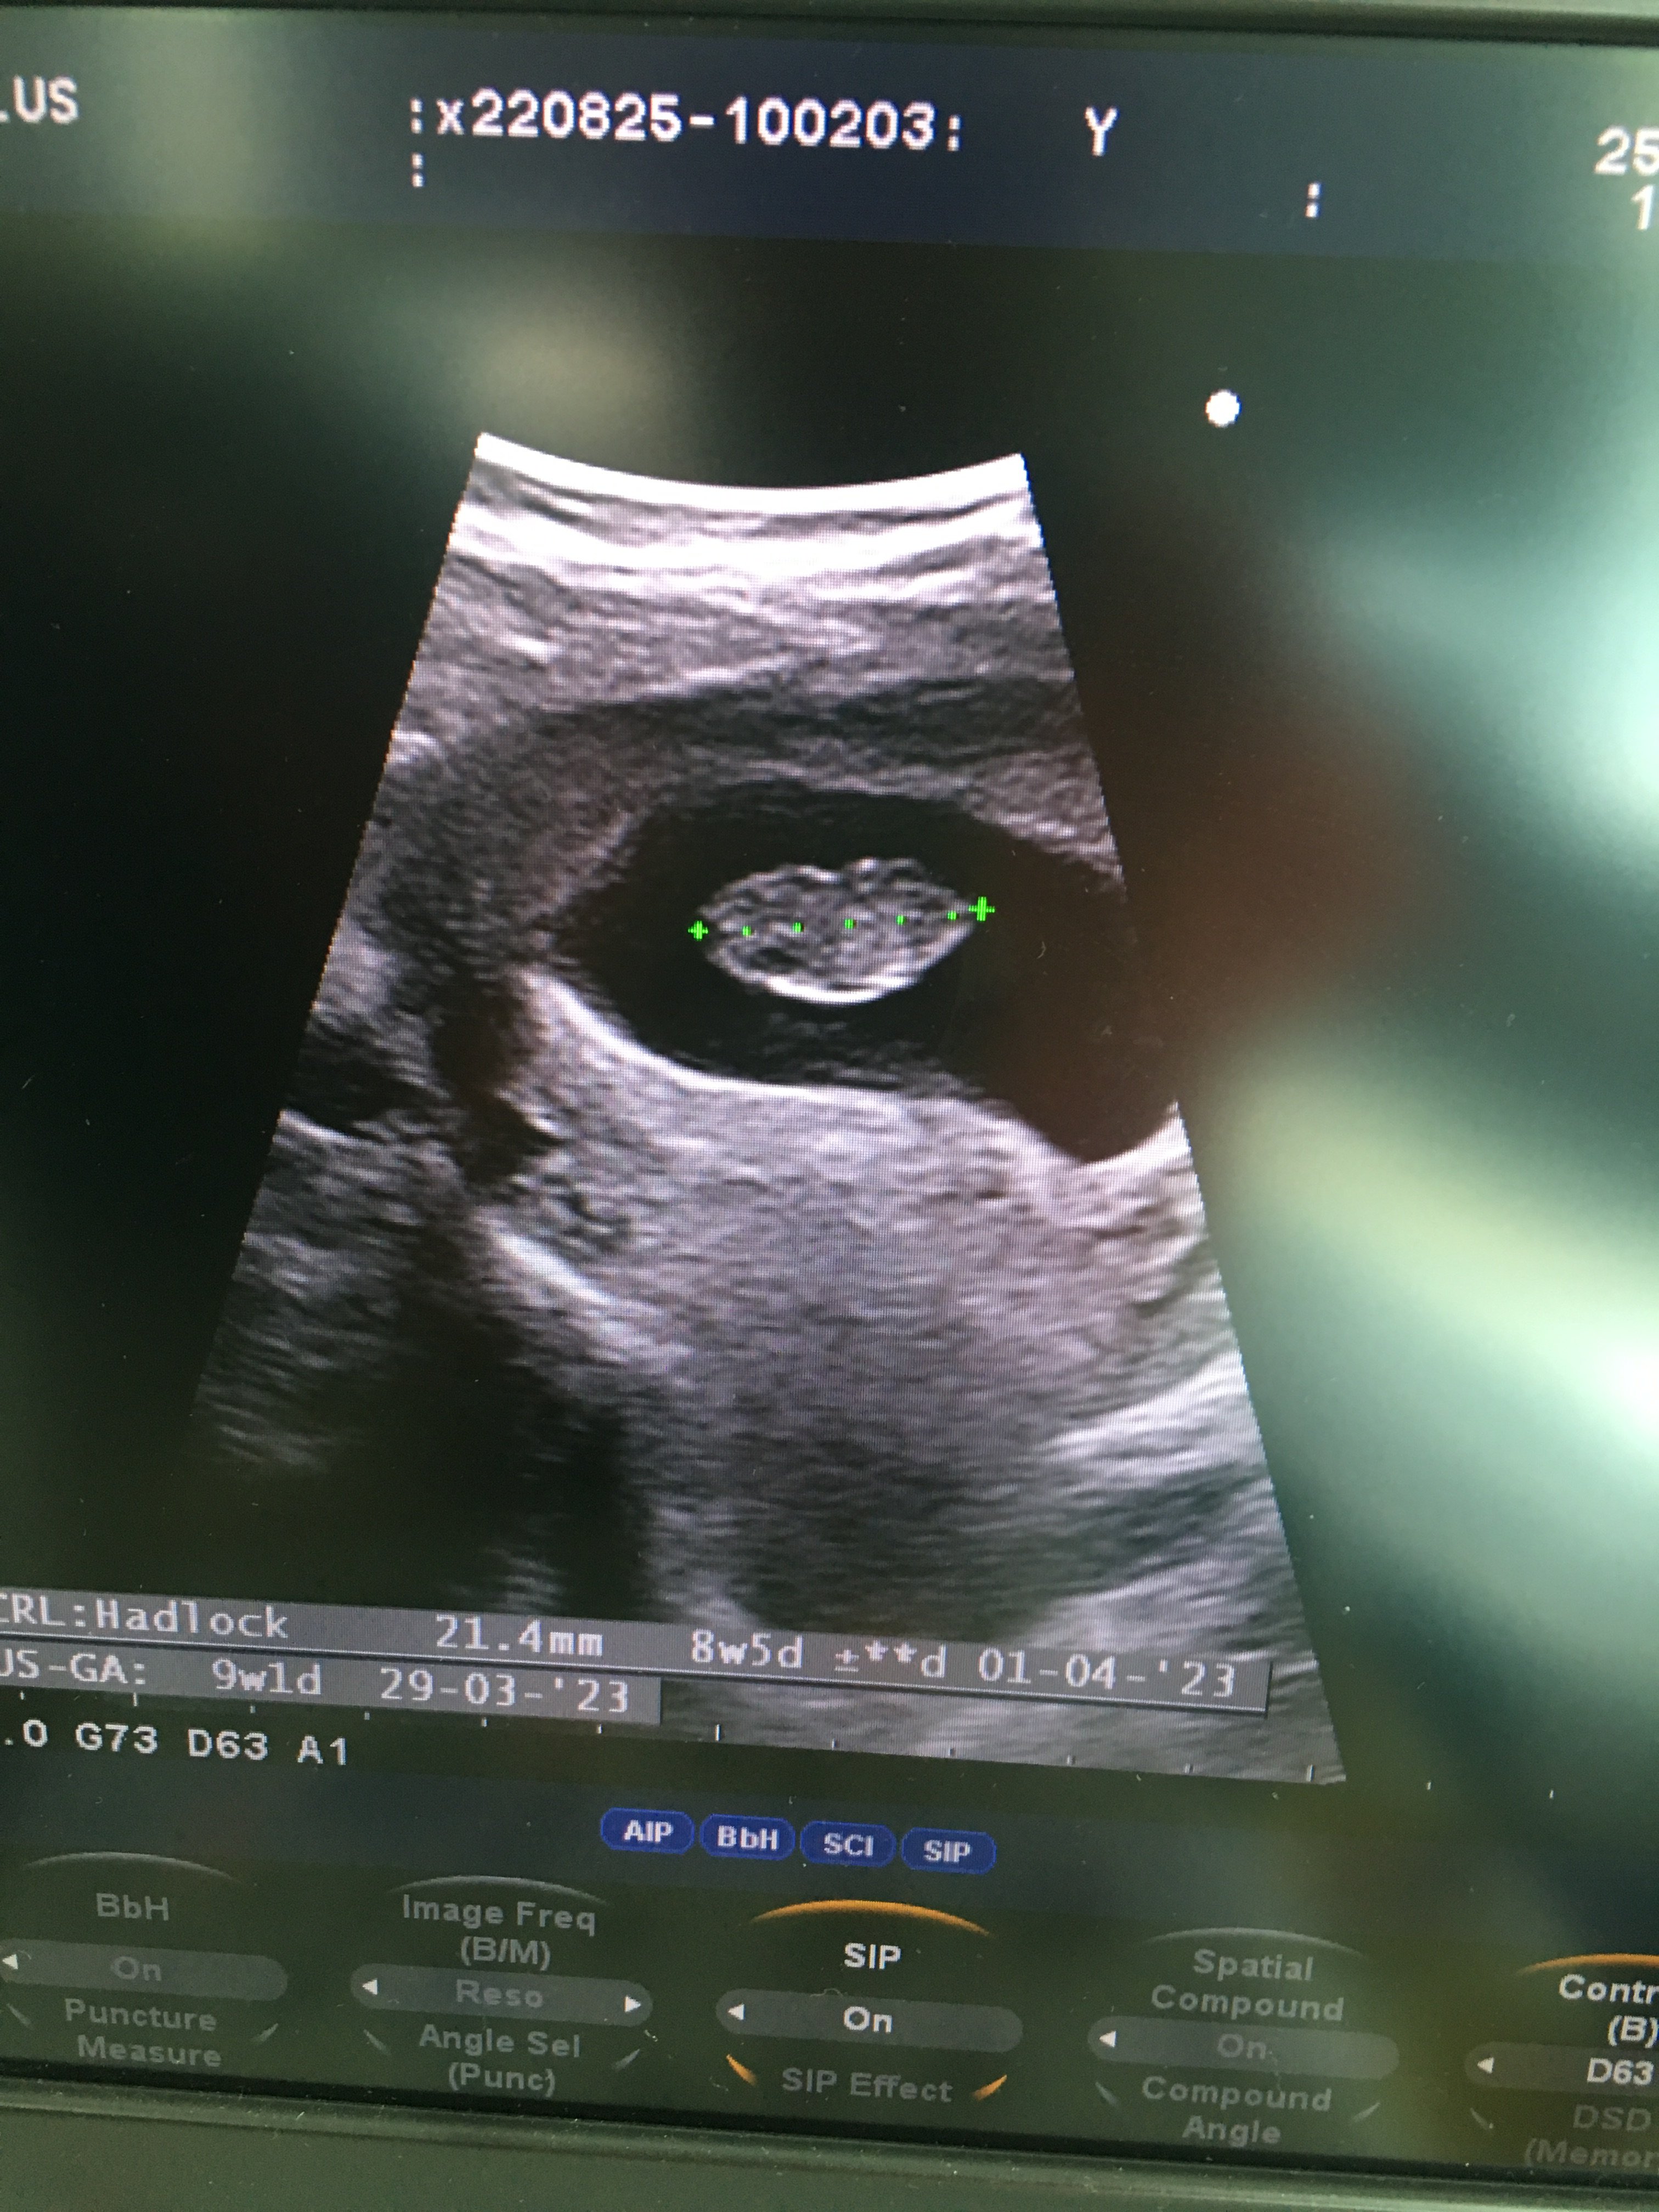

Merhaba kontrolden yeni geldim yeni ultrason görüntüsü atsam bakarmısınız acaba 8 hafta 5 günlük

• C322ECEE-B184-4942-8381-CF125DB8A380.jpeg

C322ECEE-B184-4942-8381-CF125DB8A380.jpeg

1,6 MB · Görüntüleme: 183